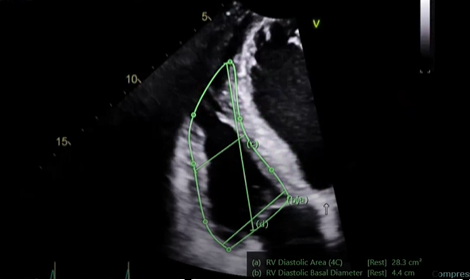

Correctly measure a RV (Base, mid and length)

what is this measurement for

RV focused view this will be a lateral tilt

do a base, mid, and length measure along with the fractional area of change measurement (FAC%)

measure at the end of the QRS / end-diastole

RV diastolic area, trace it

when doing the base measurement do not bring it down past the annulus you will be right at the base of the actual ventricle

mid length, in the middle of the ventricle

and then perform the diastolic length, so RV apex all the way down

the area and the diastolic area and the systolic area give us fractional area of change this is showing our radio function, how the msucle is moving inwards that is our radial function that is our FAC %